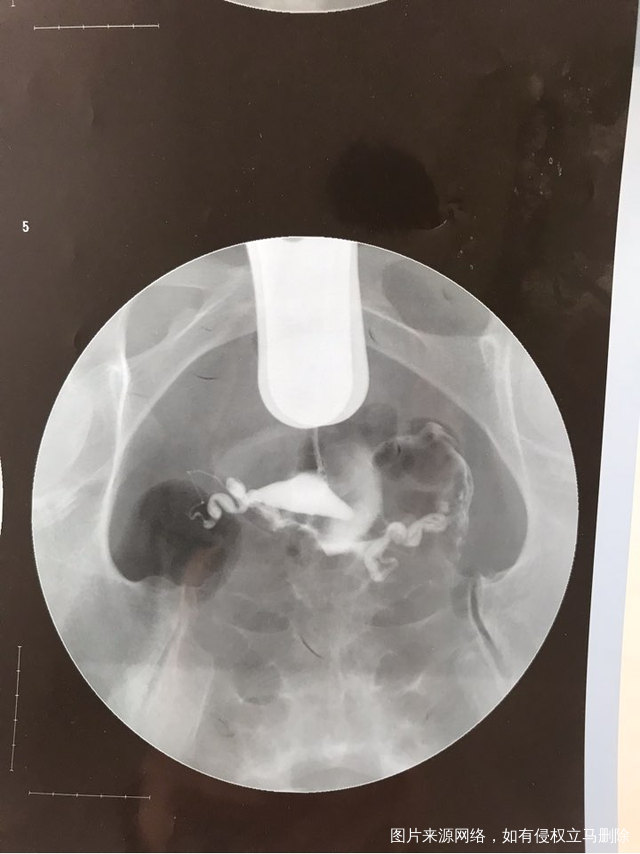

输卵管造影显示这样还能自己怀孕吗